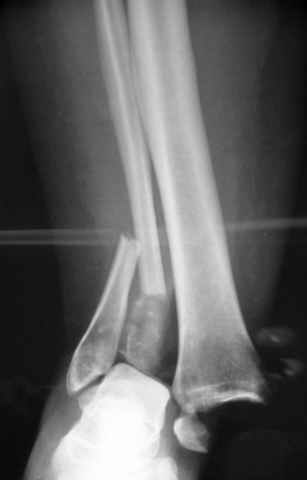

Dear all,40 y.o. man had sustained this terrible fracture falling from a motorbike.

Closed fracture.

We have put his limb in traction.

After some days of traction I would like to insert an external fixator (I think a circular one instead of a monoaxial one, because of the multiplanar situation of the fracture).

This is really Pilon Fx (C3.3; the high energy and the extent of distal tibia comminution are defining it).